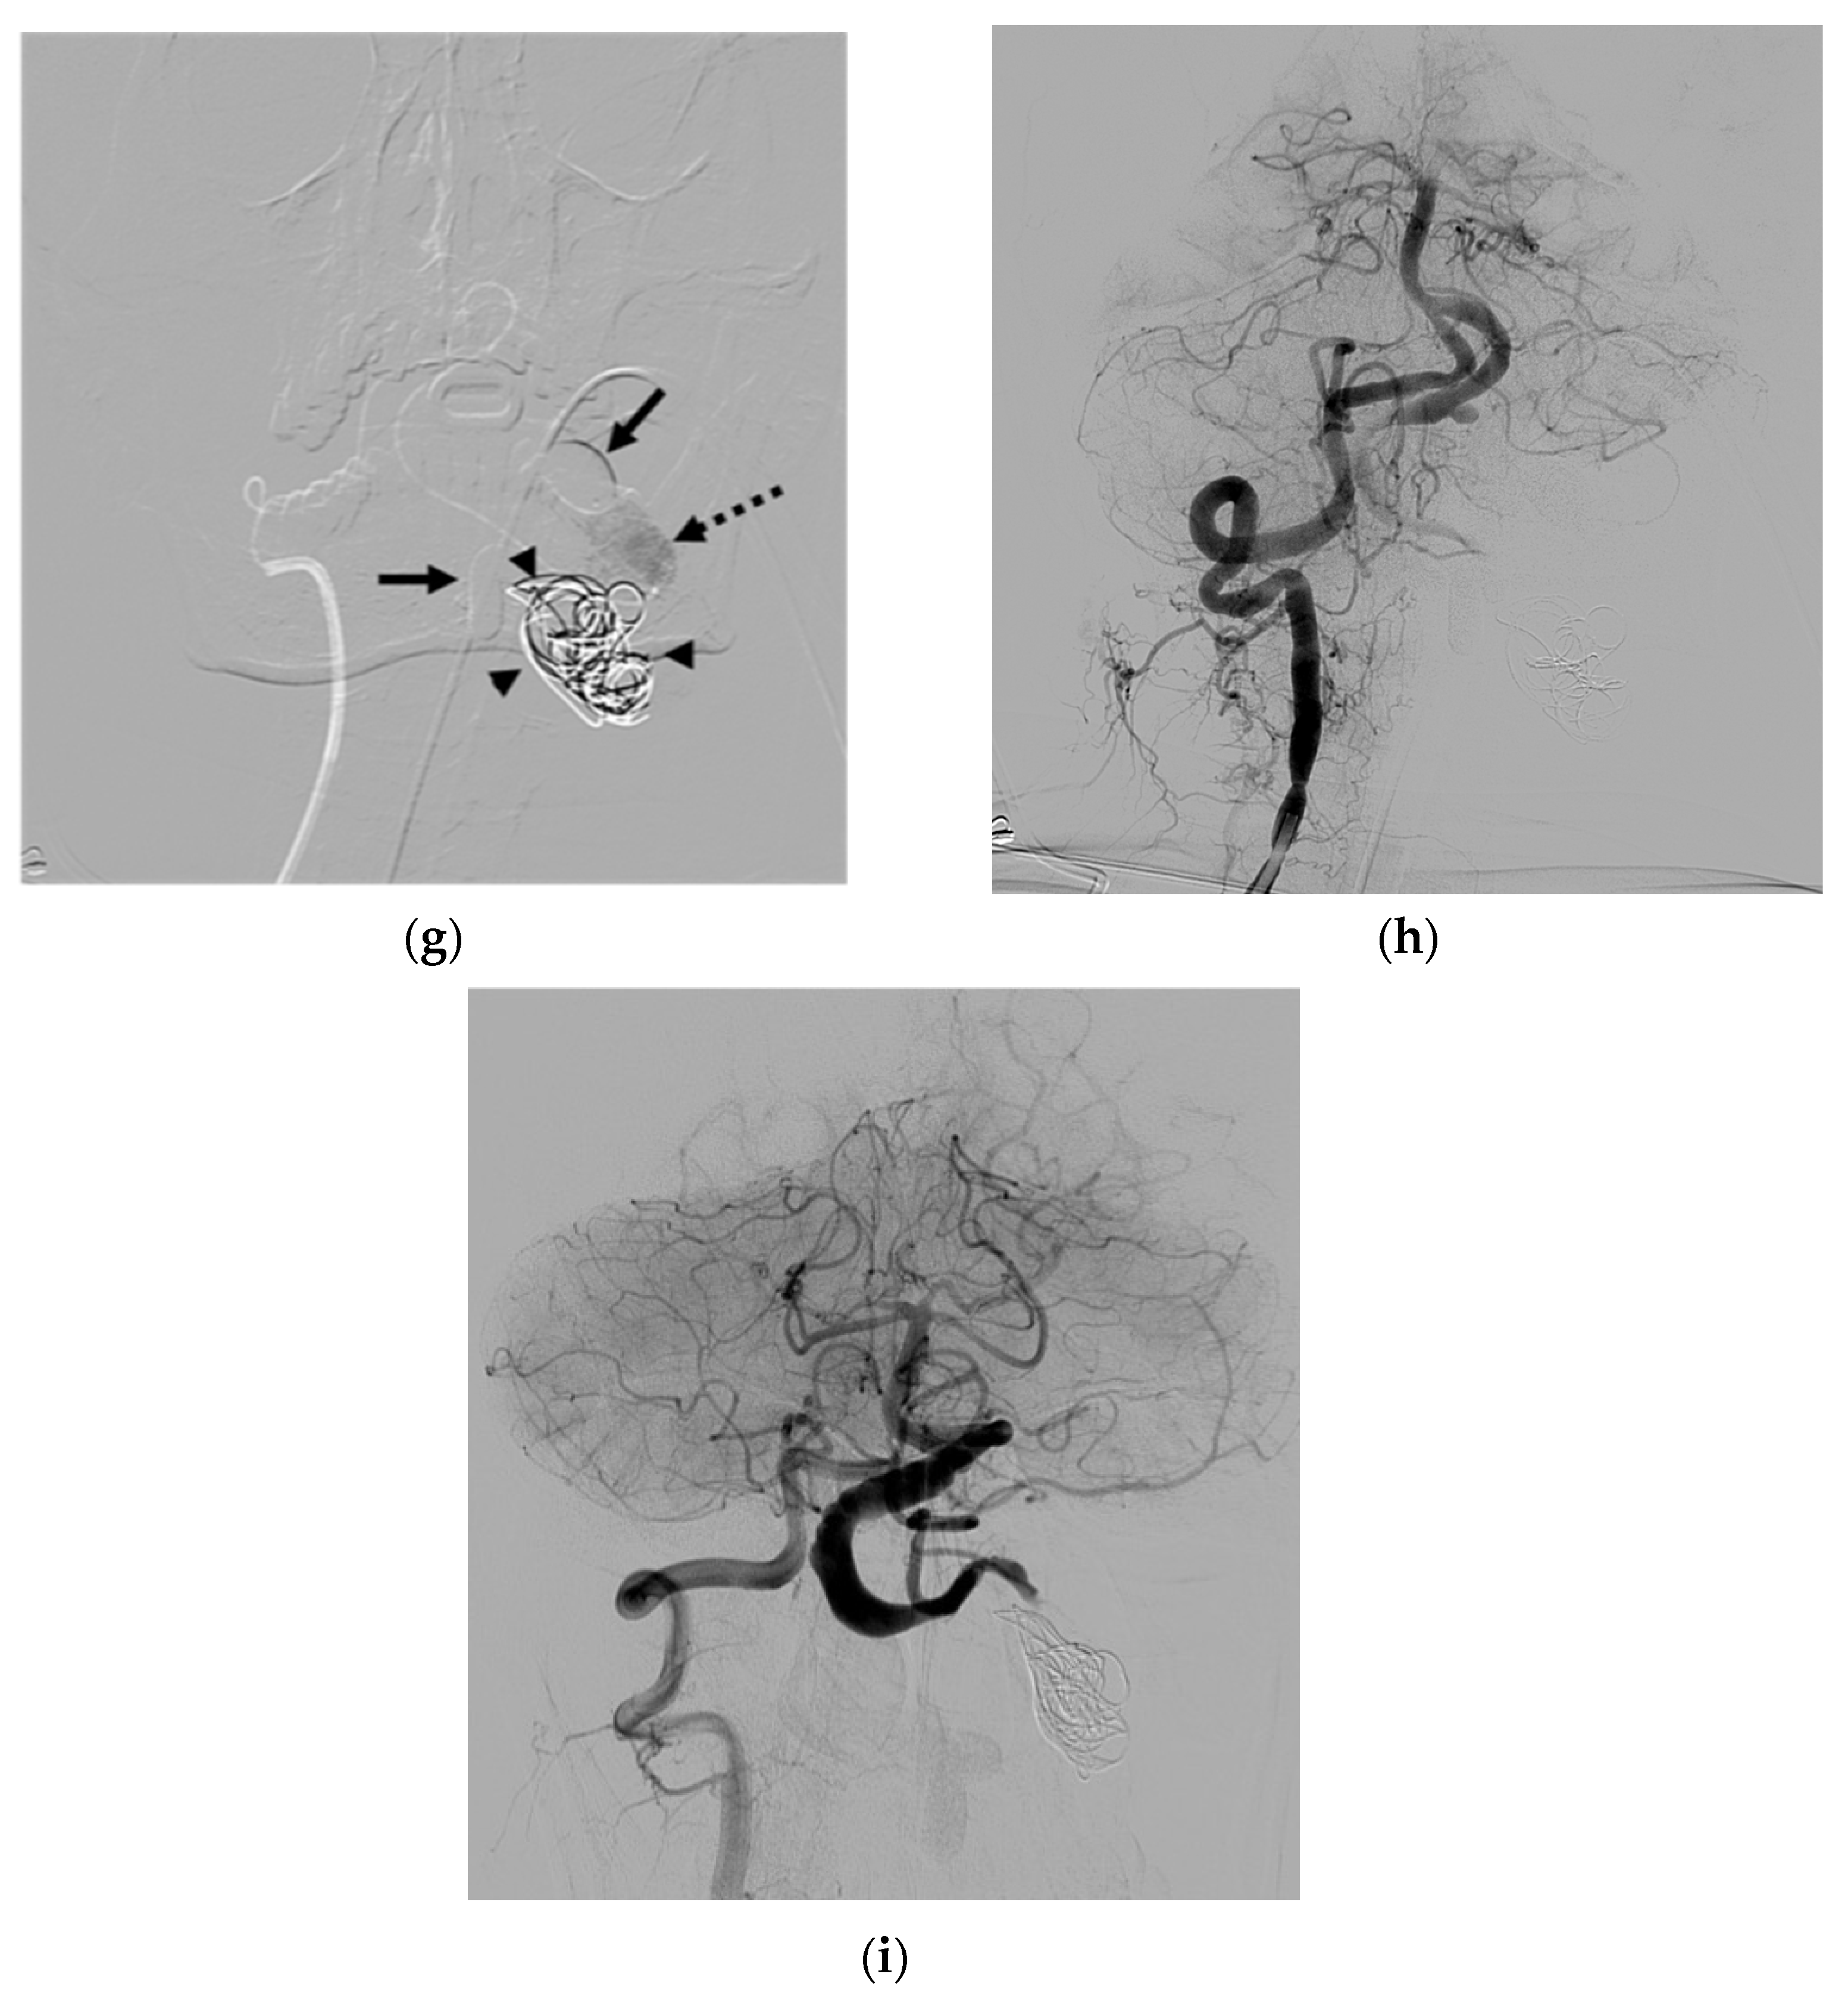

| 6 | M | 42 | Proptosis of left eye | Unknown | S | Epidural veins; VVP to IPS; CS and left SOV | N | B and C | O | Improved | None |

| 8 | F | 33 | Neck mass; tinnitus; paresthesia of left arm; ataxia | NF-1 | S | IJV; VVP with venous pouch | Y | B, C, and NBCA | O | Improved | Vertigo |